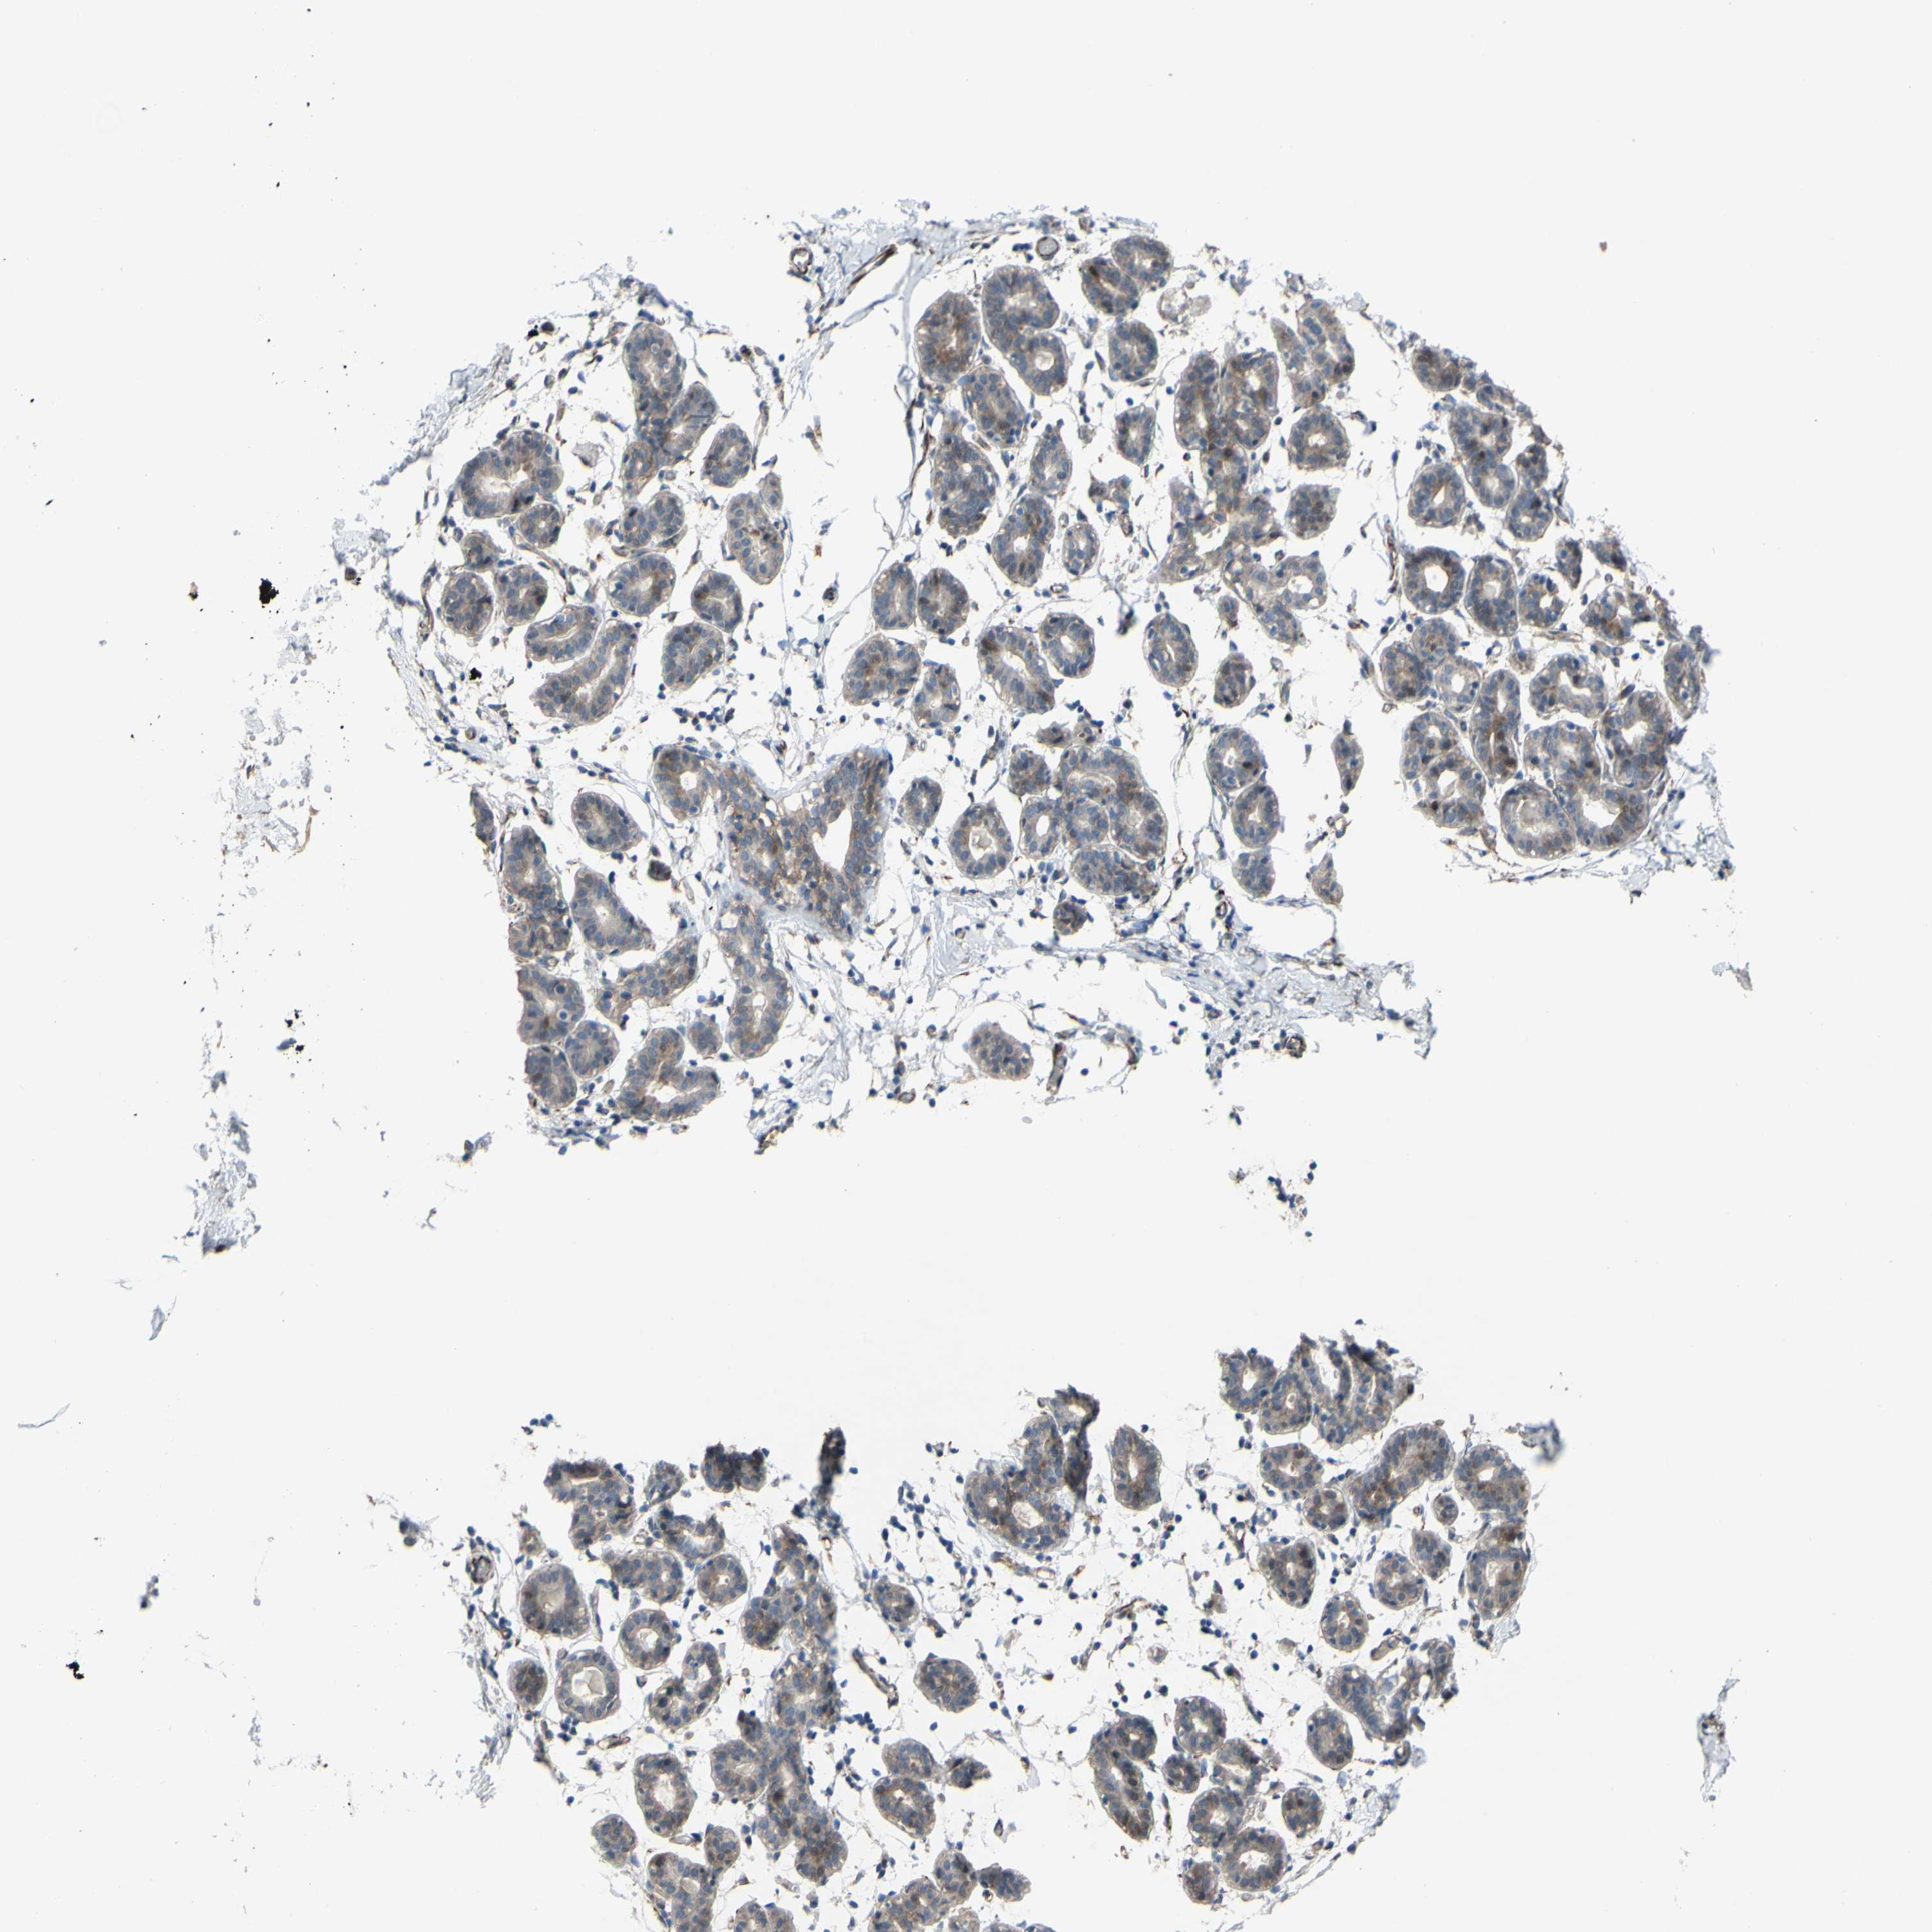

CDCP1